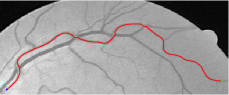

In this paper, we propose a coherence-penalized minimal path model, where the associated minimal paths favour to pass by a vessel that is located in the flatten region of an external feature map. We observe that along a piece of retinal vessel, the values of gray levels vary slowly. More specifically, retinal arteries have lower contrast of gray levels than veins due to the blood materials and imaging modality. In other words, in some extent the arteries and veins are distinguishable in terms of vesselness values. Such an observation can be used to solve the short branches problem that the minimal paths associated to a metric may pass through segments belonging to different vessels as shown in Figs. 1b and 1c. Fig. 1d shows the result from the proposed method, which can avoid such problem. Fig. 1a gives the artery-vein (AV) groundtruth. In this paper, we denote by blue and green dots the source and end points respectively.